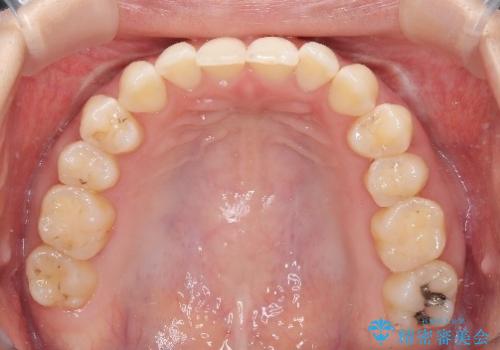

再矯正 前歯のガタツキをマウスピース矯正で治療したい

- 前に矯正治療をしたが、後戻りしてガタツキが出てきたので、治したいとのことで来院されました。

ワイヤー治療とマウスピース矯正、2通りの治療を提案させていただき、マウスピース矯正治療を希望されましたので、インビザラインによる治療を開始しました。

前歯のガタツキを改善する治療法として、マウスピース矯正が適していることが多いです。

マウスピース矯正は、金属製のブラケットやワイヤーを使用せずに、透明なマウスピースを装着して歯を移動させる方法です。そのため、目立たず、痛みも少ないです。